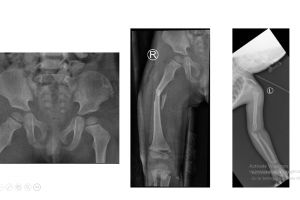

Vừa qua khoa cấp cứu bệnh viện Nhi đồng Thành phố, tiếp nhận một trường hợp trẻ C. Th. Ph., 4 tuổi, nam, cân nặng 16 kg, ngụ tại Long An, được chuyển từ bệnh...